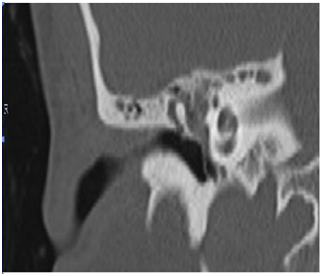

There was no negative effect of medication on the patient during the treatment. After two months of treatment, the normal hearing was restored and type A of tympanogram was obtained. The results of CT scan image of the ear are presented on Figure 3 & 4.

Figure 3 MEM, 50 yrs female, OMC with polyps, R ear after treatment.

Figure 4 M EM, 50 yrs, female, OMC with polyps.

As immunosuppressive drug the option was a low-dose prednisolone with its glucocorticoid effect.9,10 As it is visible in the Figure 3 & 4, a resolution of the disease is obtained with no need for surgery. The patient had no recurrence of the ear disease.